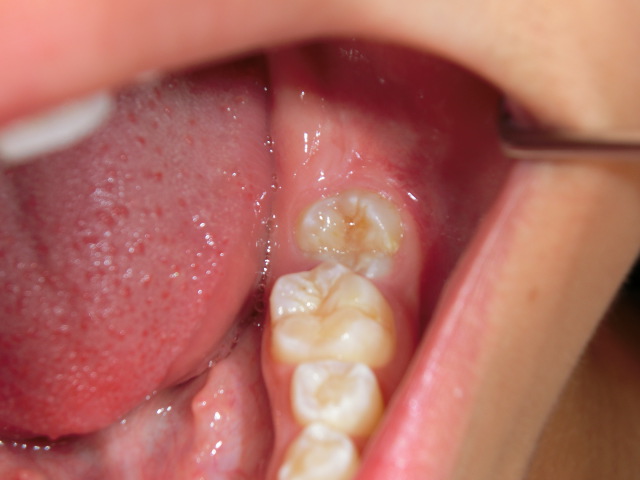

症例1 |

左下顎水平埋伏歯に起因する智歯周囲炎により、顔面腫脹、開口障害、嚥下障害を主訴に受診。

当初、局所洗浄と抗生剤の内服を行っていましたが疼痛著しく、腫脹の瀰漫性増大をきたしました。

そのため抗生剤を点滴静注し、消炎をはかりました。

消炎後4週間目に左下水平埋伏智歯の抜歯を行いました。